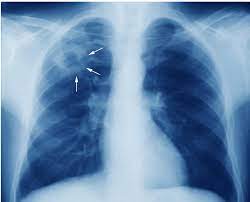

Khi có các triệu chứng trên cần tới các cơ sở y tế chuyên về lao để được khám và điều trị. Thường bệnh nhân sẽ được cho chụp X quang phổi. Nếu phổi có tổn thương dạng thâm nhiễm, nốt, hang nghi ngờ lao sẽ được cho xét nghiệm soi đàm tìm vi trùng lao. Nếu có vi trùng lao trong đàm sẽ được khởi động điều trị lao phổi.

Trường hợp nếu không thấy vi trùng lao trong đàm thì bác sỹ sẽ cho làm thêm các xét nghiệm khác như chụp CT phổi, nội soi phế quản lấy dịch rửa phế quản làm xét nghiệm. Sau đó sẽ được hội chẩn để chẩn đoán và điều trị lao nếu cần.